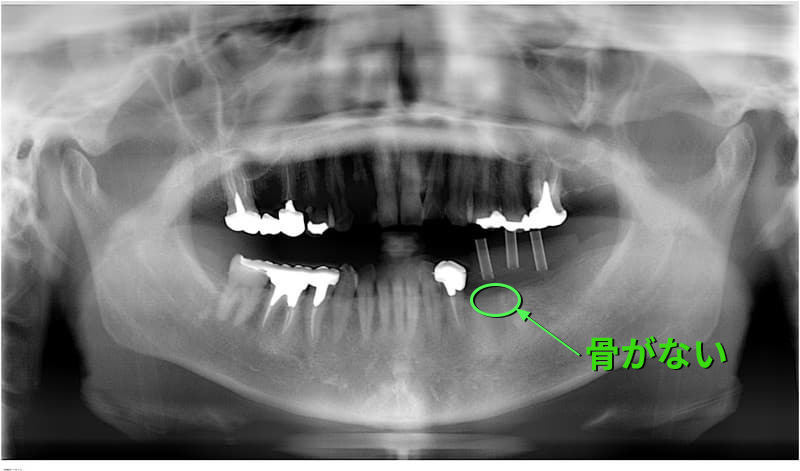

病歴や健康状態に関する問診、口の中の検査、レントゲン写真や歯型の採取